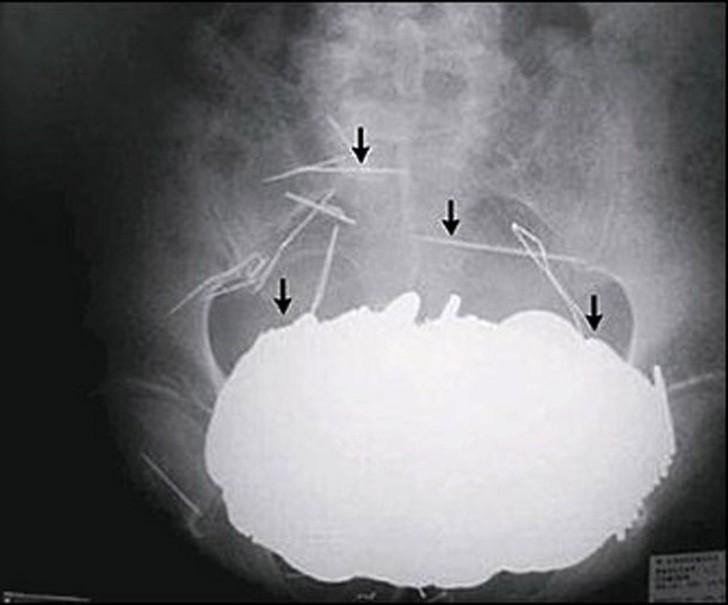

12. Столовые приборы.